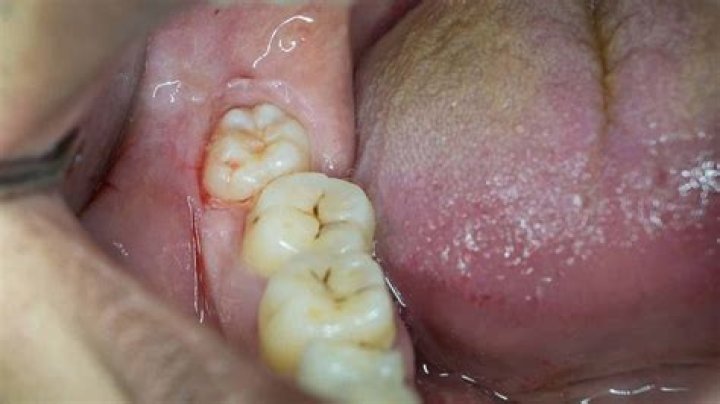

What does wisdom teeth coming in feel like?

Even if your wisdom teeth emerge through your gums normally, they can cause you to feel various mild symptoms. You might experience some mild pain, the feeling of pressure in your mouth or jaw, or a dull throbbing sensation in your gums, close to the opening of your throat or in your jaw bone which is nearby.